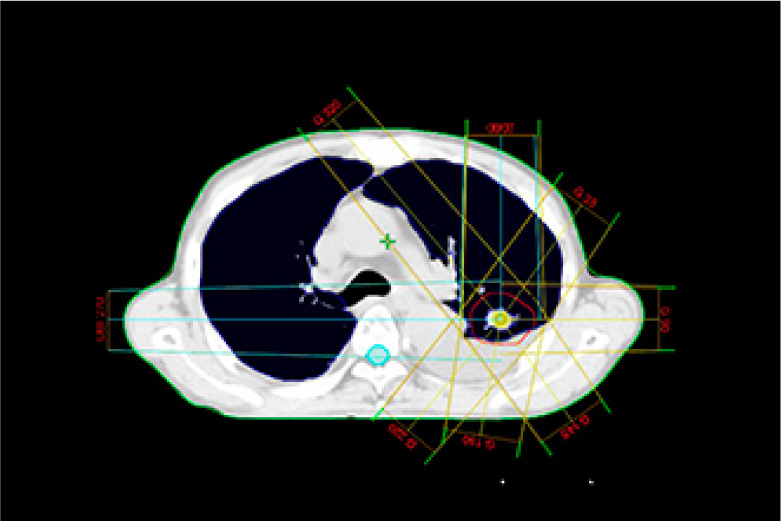

放射線治療

放射線治療とは身体できた病巣部に放射線を照射しがん等の病気を治す治療法です。

手術と比較し身体への負担が少なく病巣部を安全かつ効果的に治療することができます。

当院で使用する放射線は高エネルギーX線及び電子線で直線加速器(リニアック)を用いて人工的に放射線を作るため目的に応じた線質、強さ、量に調整することができます。

実際の治療ではまず治療開始前にCT撮影を行い、照射する場所、範囲、放射線の量等を専用の機器を用いて決定します。(下図参照)これをもとに治療時には装置に搭載されたX線撮影装置、CT装置にて画像を撮影し3次元的に位置照合を行い計画された方向より照射します。

治療装置は360度どの方向からでも照射可能で病巣を多方向から正確に照射することで治療効果の向上、病巣周囲の正常組織の線量を減らすことができます。

治療は1回約10分程度で(初回のみ20~30分)通常1日1回で20~30回程度行います。通常照射中は痛み等特になく身体への負担は少ないですが毎日休まずに行うことが重要となります。(治療は平日のみで土日祝日はお休みです)

バリアン True Beam